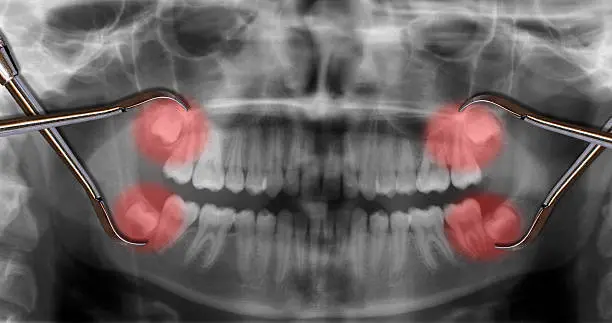

ฟันคุดคือ อะไร

ฟันคุดคือ ฟันกรามซี่ในสุด ทั้งหมด 4 ซี่ บน ล่าง ซ้าย ขวา ไม่สามารถขึ้นได้ตามปกติเพราะพื้นที่ไม่เพียงพอให้ฟันสามารถขึ้นมาได้ บางซี่อาจจะโผล่ขึ้นมาเล็กน้อย และบางซี่ถูกฝั่งอยู่ในกระดูดขากรรไกร อาจจะขึ้นตรง เอียงหรือนอนในแนวราบส่วนใหญ่ฟันคุดมักพบว่าอยู่ที่ฟันกรามซี่ล่างในสุดและพบมากสุดในช่วงอายุ ประมาณ 16 – 25 ปี หรืออาจจะช้ากว่านั้น

ทำไมต้องผ่าฟันคุด

เพื่อป้องกันปัญหาเกี่ยวกับช่องปาก ฟันผุ เหงื่อกอักเสบ ฟันซ้อมเก ไม่ควรปล่อยให้ฟันคุดฝั่งอยู่ในขากรรไกร เพราะอาจะทำให้แนวฟันอื่นเสียหายจากการดันตัวของฟันคุด และที่สำคัญคือส่งผลให้มีอาการปวดฟันคุดรุนแรง